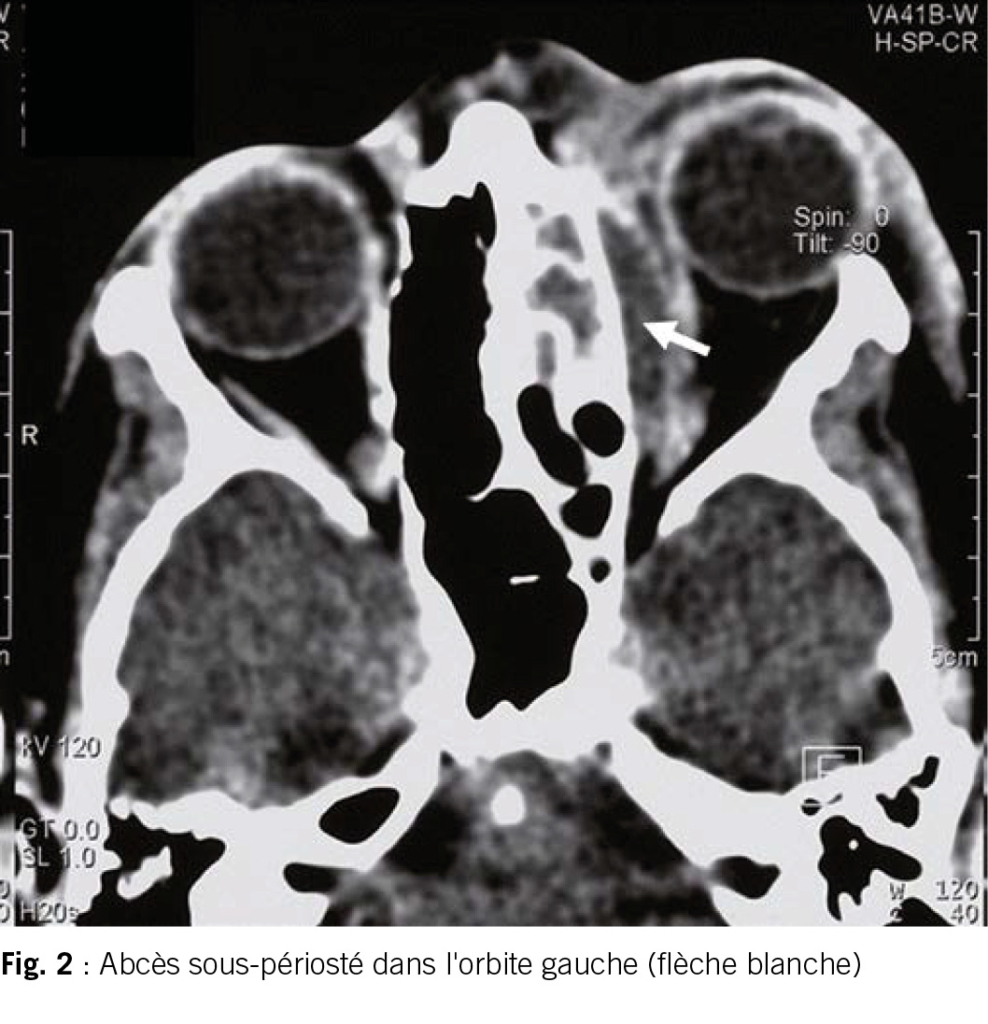

Garçon alerte, un peu abattu. Œil gauche gonflé et rouge (fig. 1). Il ne peut presque plus l’ouvrir. En ouvrant les paupières avec les doigts, on constate que les conjonctives ne sont pas irritées. Les pupilles sont de diamètre égal. L’acuité visuelle est grossièrement contrôlée et ne présente pas de particularité. La motilité oculaire est conservée, mais douloureuse. Pas de méningisme.

L’enfant dans ce cas ne peut toutefois plus ouvrir activement l’œil et présente des mouvements oculaires douloureux, ce qui plaide en faveur d’une complication orbitaire pertinente. Et c’est ainsi que la suite de l’examen d’urgence à l’hôpital révèle au scanner un gros abcès sous-périosté dans l’orbite gauche (fig. 2). L’abcès est soulagé chirurgicalement et traité par antibiotiques. Une lésion permanente de l’œil peut être évitée.